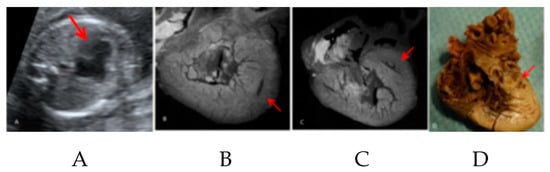

- Hutchinson, J.C.; Ashworth, M.T.; Sebire, N.J.; Arthurs, O.J. Multiple Cardiac Rhabdomyomas Visualised Using Micro-CT in a Case of Tuberous Sclerosis. Fetal Diagn. Ther. 2017, 41, 157–160. [Google Scholar] [CrossRef]

| Hutchinson JC 2017 [34] | 1; isolated heart | 1 | NP | NP | 35 | NP; NP | Iodine agent; NP; NP | NP | NP | NP | Case report | Descriptive analysis | NP | 1st description of cardiac tumor identification using micro-CT |